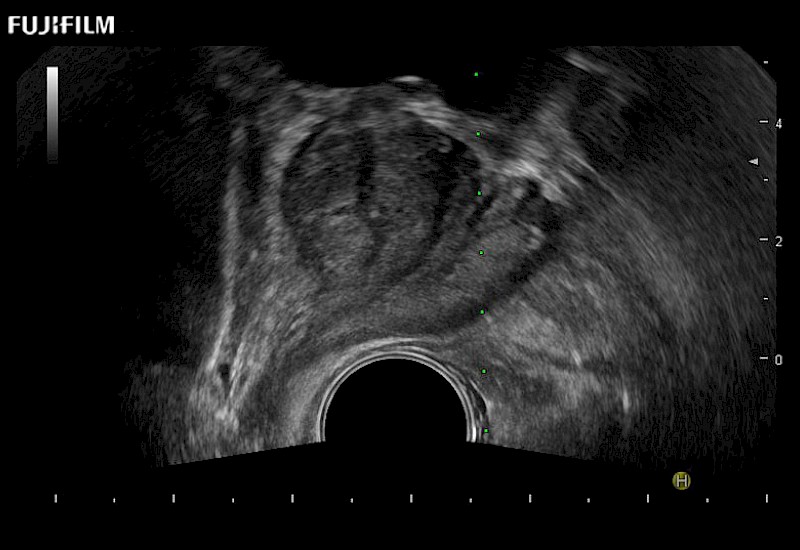

Exclusive 200° FOV end-fire prostate biopsy transducer.

Main Specifications:

Provides real-time imaging of both the sagittal and transverse planes